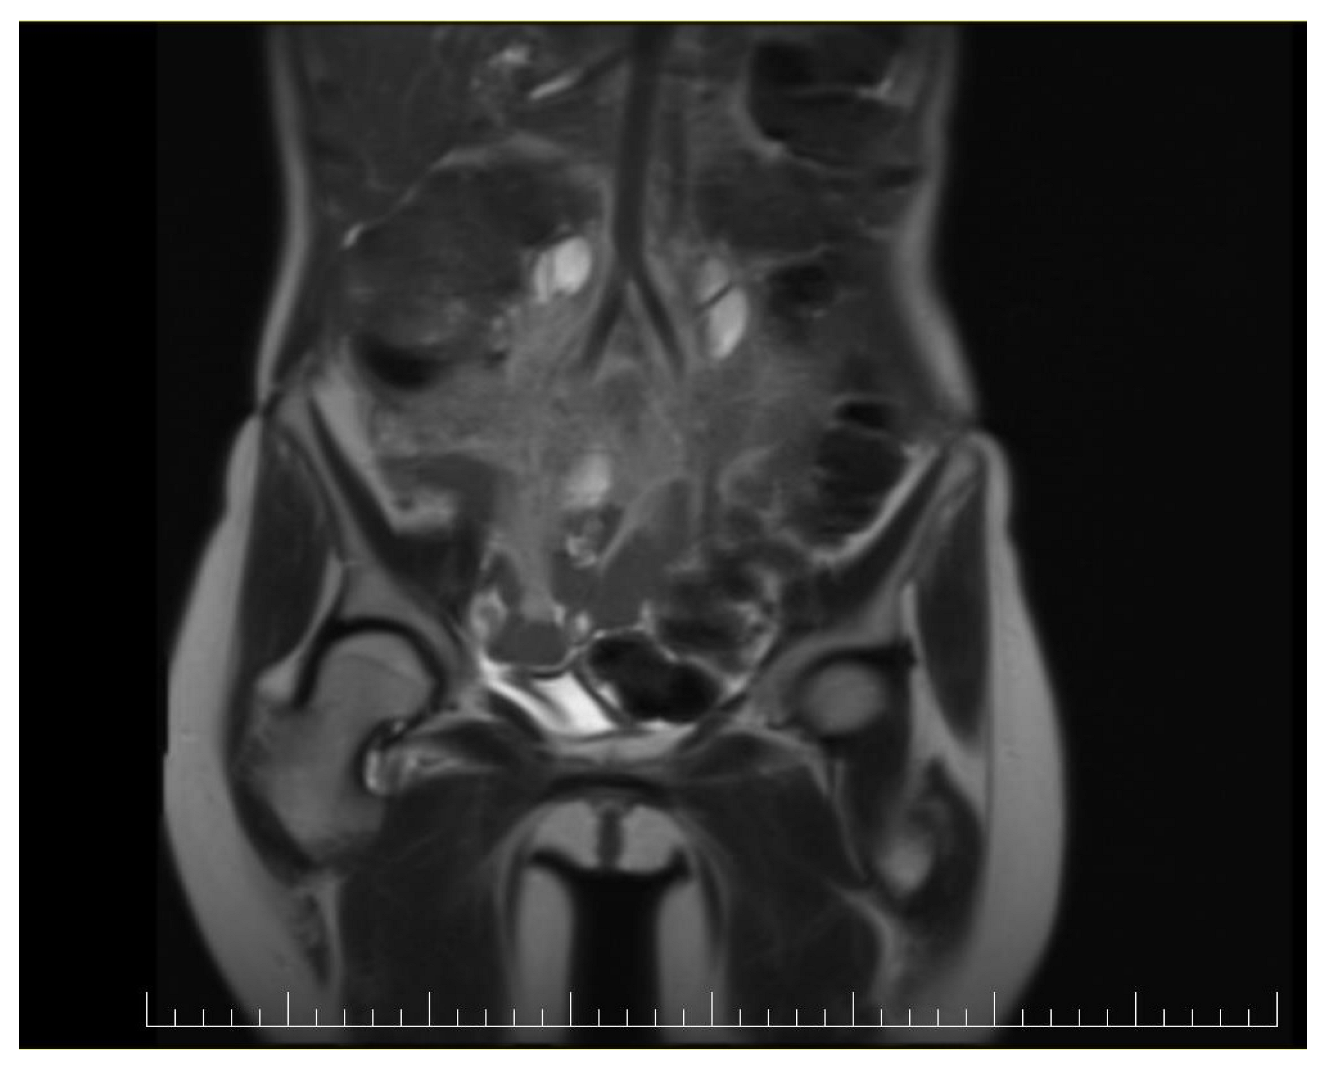

This case report details the presentation, diagnosis, and management of a 44-year-old female who experienced a relapse of colonic cancer with peritoneal carcinomatosis in 2021, two years after the initial diagnosis. The patient exhibited specific symptoms indicative of disease recurrence. In 2019, the patient underwent surgical resection and received adjuvant chemotherapy for colonic cancer. Despite an initial period of remission, in 2021 she presented with symptoms such as abdominal distension, persistent abdominal pain, and changes in bowel habits. Imaging studies, including CT scans, confirmed the presence of peritoneal carcinomatosis, indicating a relapse of colonic cancer along with two suspected tumorous formations localized in the ovaries (Figure 1 and Figure 2). Upon relapse, the patient underwent a thorough diagnostic workup, including imaging studies and tumor marker assessments. Elevated levels of carcinoembryonic antigen (CEA) of 5.44 ng/mL and CA-19-9 of 58 U/mL were observed, supporting the diagnosis of colonic cancer recurrence with peritoneal carcinomatosis.

Figure 2.

Preoperatory sagittal view of a CT image presenting a giant ovarian mass.